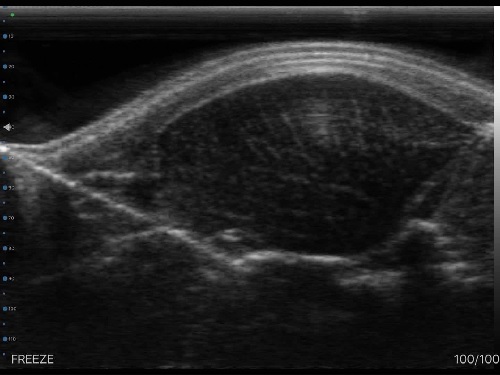

ECOGRAFO PROVETSCAN SU-3 SONDA WIFI LINEARE

Ecografo Provetscan SU-3A ad uso veterinario, con sonda WIRELESS lineare

Con immagine accurata e di alta qualità per la misurazione del grasso dorsale, del diametro e dell’area del lombo di suini e bovini. Completo di sonda wi-fi per iPad mini, cover protettiva, imbragatura di fissaggio per un metodo di lavoro più agile e una comoda valigetta di trasporto.